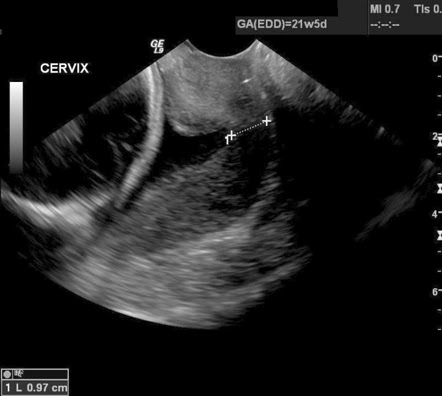

Is there anyone out there who has had these shortening cervix symptoms such as funneling, cervix opening.all these worries that most of these women have had and still has gone full term.

Closer to ovulation you will notice that your cervical opening begins to enlarge. Is it open or closed? The cervical position changes during after ovulation, the cervix becomes firm, the uterus opening gets closed with mucus, and the cervix drops.